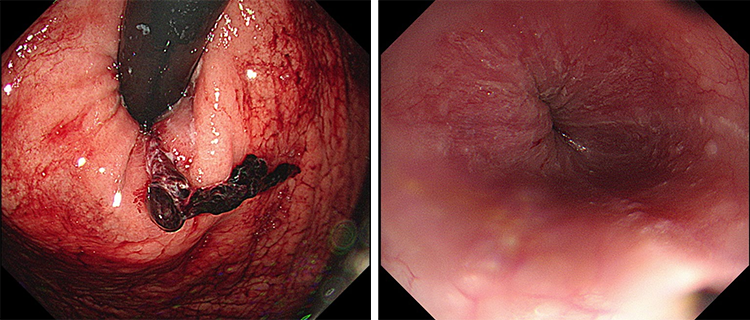

내원시 혈압 74/50 mmHg, 심박수 122회/분, 체온 섭씨 37.0도 확인되었고, 의식수준 은 명료하였습니다. 수액 치료 후 혈압 116/75 mmHg, 심박수 88회/분으로 회복되었 습니다. 혈액검사상 혈색소 14.3 g/dl, 혈중요소질소 13.6 mg/dl 크레아티닌 1.09 mg/dl 확인되었습니다. 이에 상부위장관내시경을 시행하였습니다. [그림1]

[그림 1] 상부위장관내시경상 위식도접합부의 궤양양 병변과 출혈이 확인됨.

이에 출혈성 병변에 대해 Hemoclip을 이용한 내시경적 지혈술을 시행하였습니다. [그 림2]

[그림 2] 내시경적 지혈술을 시행한 후의 사진